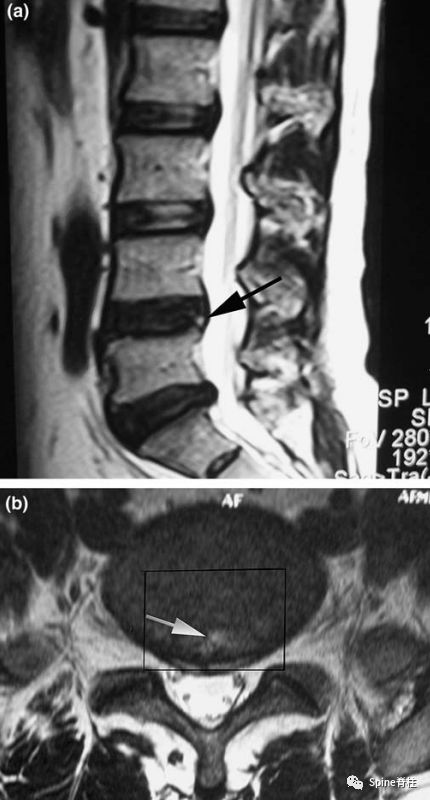

箭头所指为HIZ高信号区,是纤维环破裂引起的腰痛明显的磁共振征象

但值得注意的是,腰椎MRI阅片看到椎间盘HIZ高信号区时,不要仅关注T2加权像,也应关注T1加权像。因为只有在T2局限性高信号、T1局限性较低或等信号(single-HIZ)才意味着通常所指的纤维环破裂伴随肉芽组织长入,HIZ诊断椎间盘源性腰痛才有指导价值。

(Peng B. Spine 2006;31(5): 560-66)

椎间盘造影后CT平扫所显示破裂的纤维环(即为疼痛的椎间盘),且造影剂流经至HIZ高信号区,提示椎间盘源性腰痛的诊断。